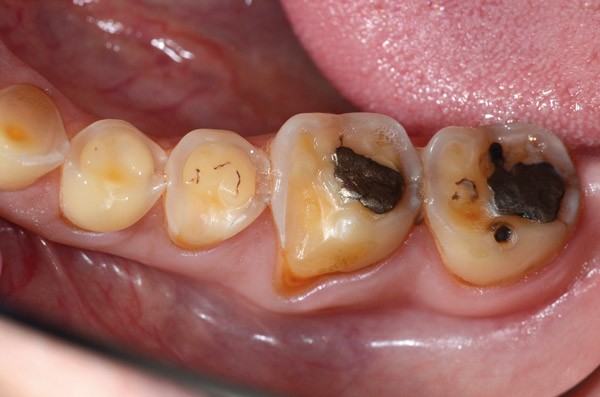

À l’examen clinique (fig. 2 à 4), on observe :

– l’absence de 17, 27 et 47 (suite de lésions carieuses volumineuses) ;

– un parodonte sain ;

– des érosions sévères généralisées, symétriques et bilatérales (occlusales, palatines et vestibulaires au maxillaire) ;

– des lésions carieuses débutantes de site 3 ;

– des obturations préexistantes infiltrées ;

– une vitalité pulpaire conservée sauf au niveau des prémolaires maxillaires ;

– une usure des bords libres des incisives mandibulaires

L’examen radiographique (bilan rétro-alvéolaire) objective des lésions carieuses secondaires sur 16 et 36 ainsi qu’une lésion inflammatoire périapicale d’origine endodontique sur 37 (cliniquement asymptomatique).